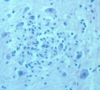

Progressive Multifocal Leukoencephalopathy

Opportunistic JC virus

Invasion and destruction of oligodendrocytes

JC virus inclusions in oligodendrocytes